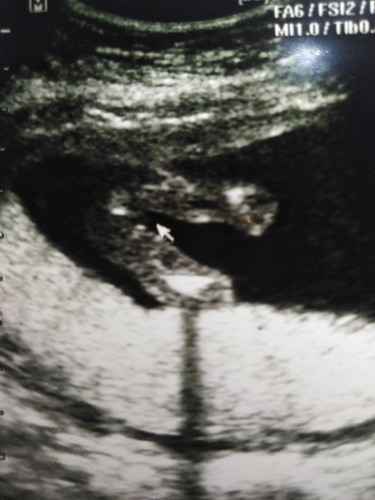

แม่ๆว่าผลอัลตร้าซาวเป็นผู้หญิงหรือผู้ชายค่ะ (คุณหมอยังไม่แน่ใจเลยไม่ได้บอก)

ดูยากจังค่ะ

ดูยากค่ะแม่